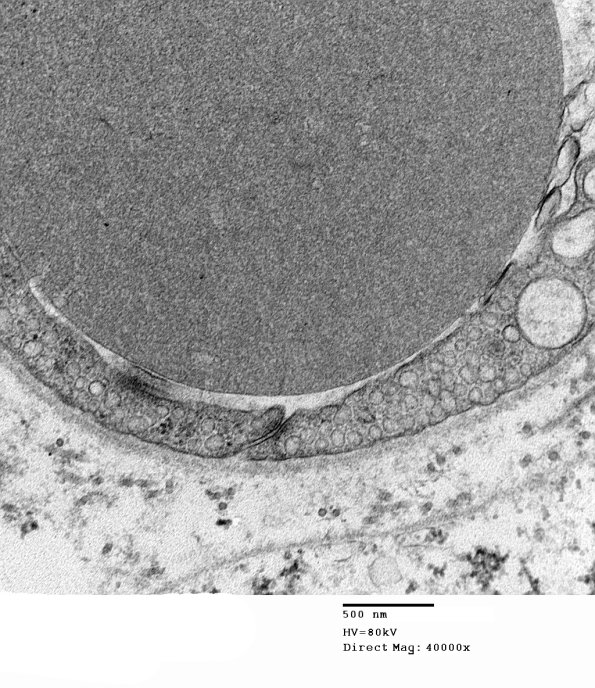

Increased magnification demonstrates a tight junction. Note the increased numbers of endothelial cell micropinocytotic vesicles.